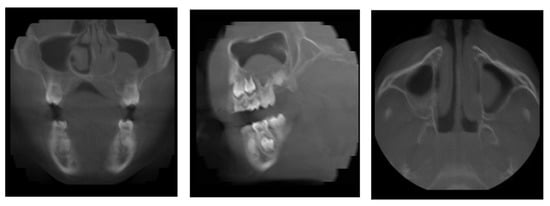

The 11-year-old patient was referred to the Children’s Dental Clinic with suspected inflammation of the periapical tissues of the region of the left premolar of the mandible. Clinical evaluation revealed hypermobility of teeth 34 and 35 (FDI) with enlargement and redness of gingival tissue of both the vestibular and lingual side of the alveolus with pain symptoms. Teeth with no signs of caries lesions were not tender to percussion, the vitality tests were inconclusive, and no palpable lymphadenopathy was noticed. A cone beam computed tomography (CBCT) examination (NewTome 3G, QR Verona, Italy, 110 kV, 2 mA, 18 s) revealed root resorption of tooth 35 and an area of extensive demineralisation in the region of 33–36 with loss of trabecular bone pattern, destruction of buccal, and thinning of the lingual cortical plates (Figure 1, Figure 2 and Figure 3). On the basis of the clinical examination and the unusual features of the X-ray examination, the diagnosis was extended to include a biopsy of soft and hard tissue. A histological examination revealed Burkitt’s lymphoma. An extent examination using 2-deoxy-2-[fluorine-18] fluoro- D-glucose integrated with computed tomography (18F-FDG PET CT), magnetic resonance imaging (MRI), and ultrasonography (USG) revealed a disseminated tumour process with infiltrates in the left palatine tonsil, head of the pancreas, stomach wall, and right pleura. On the basis of the results of the extended examination and according to the European Intergroup for Childhood Non-Hodgkin Lymphoma (EICNHL-COG Inter-B-NHL-2010) therapeutic protocol, the patient was classified into the B-High therapeutic group, and a 7-day cytoreductive prephase COP (Encorton, Cyclophosphamide, and Vincristine) was initiated. After completing the prephase, significant regression of the primary lesion was observed. Subsequently, the patient completed two cycles of R-COPADM (Rituximab, Vincristine, Methotrexate 3 g/m2, Cyclophosamide, Doxorubicin, and Encorton) and two cycles of R-CYM (Rituximab, Encorton, Methotrexate, and Cytarabine) treatments. The patient responded well to treatment, and remission was achieved. Now, five years after initial diagnosis, he is undergoing regular check-ups, including dental examinations. The intraoral lesion resolved completely because of chemotherapy, and no surgical treatment was performed (except for initial biopsy taking).

Figure 2. Patient, 11 y.o.: Axial image from CBCT examination with loss of trabecular pattern and thinning of cortical lingual and buccal plates in the region of teeth 33, 34, and 35.